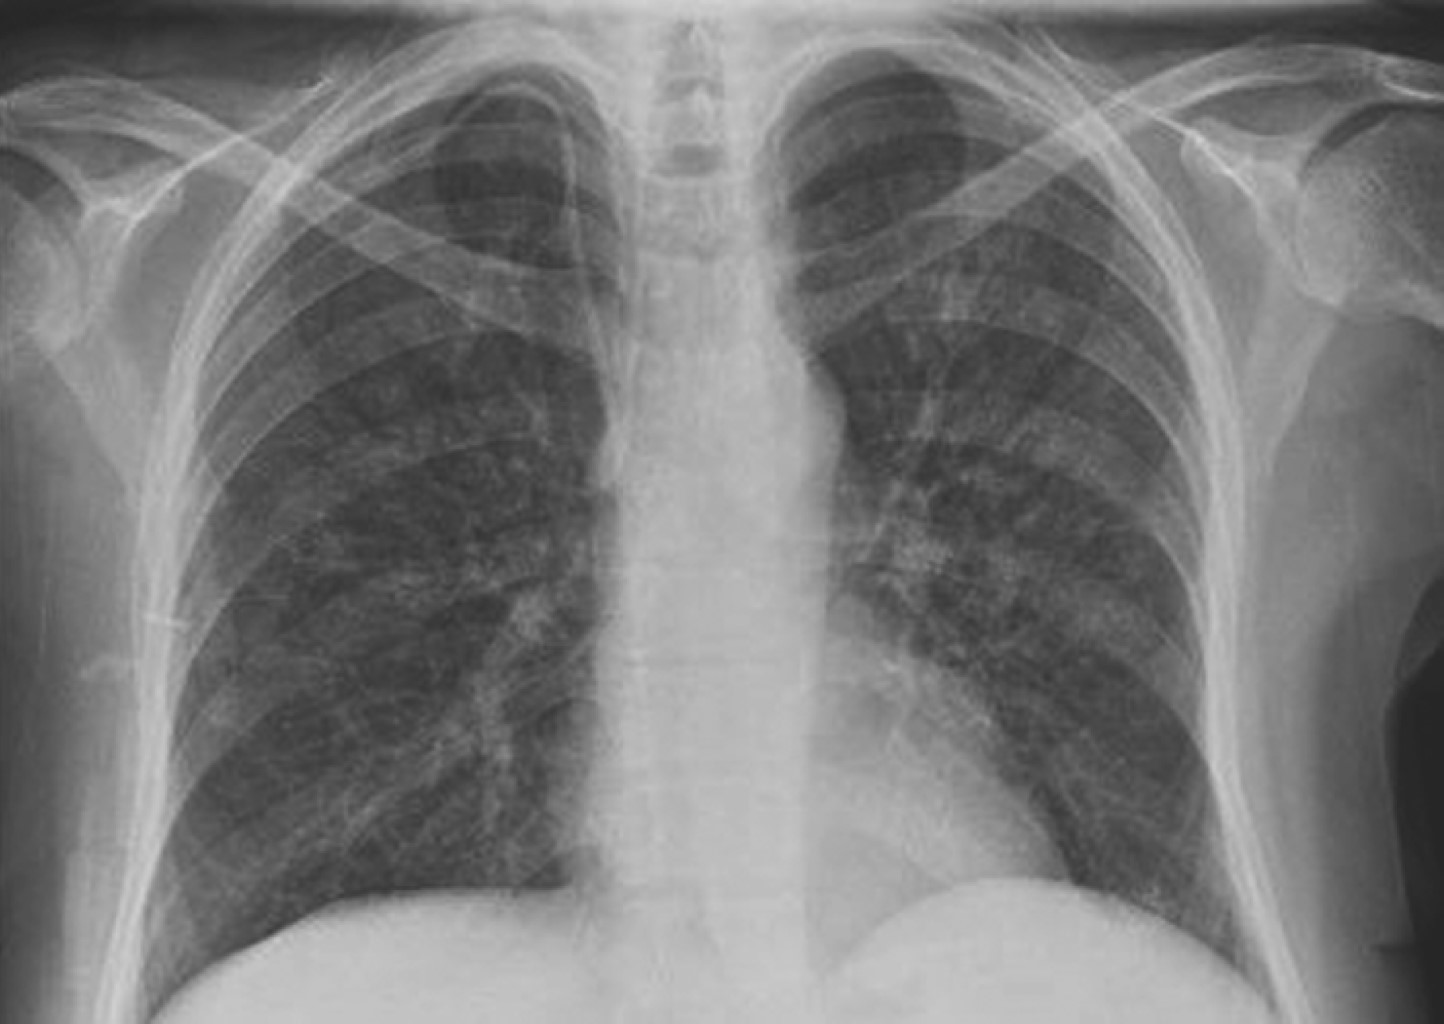

Figure 1